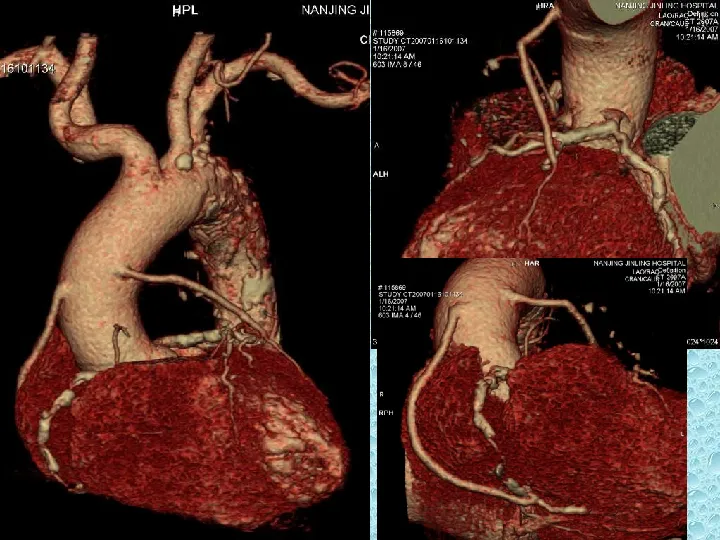

>【影像PPT】双源CT及其临床应用

【影像PPT】双源CT及其临床应用